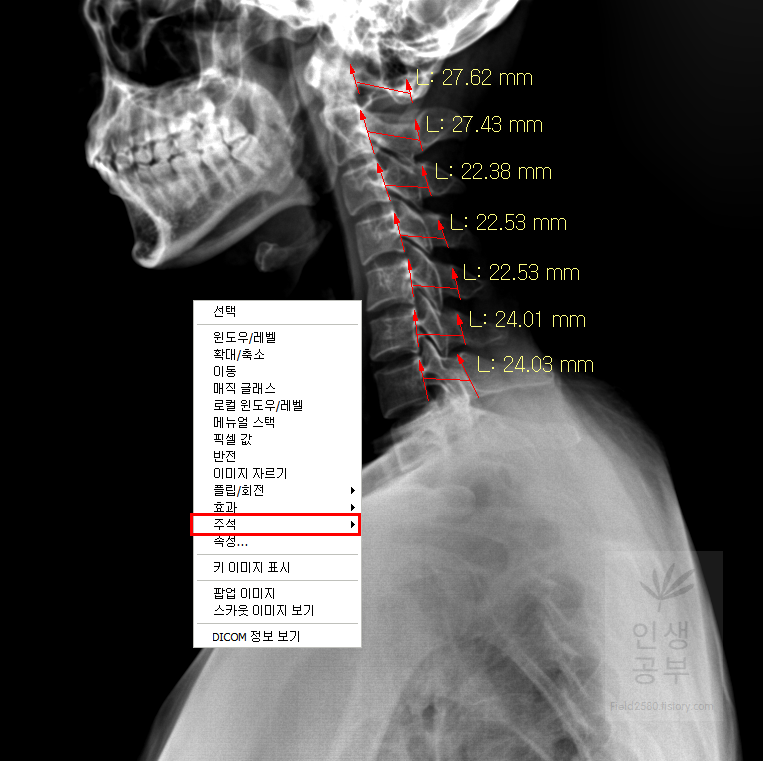

빨간색 네모칸으로 쳐진 대각선으로 그어진 줄 모양이 선을 긋거나 거리를 측정할 때 사용하는 버튼입니다.

선 긋기를 이용해서 Cobb각을 그린다고 가정했을 때 측정하려고 하는 곳을 처음에 누르고 드래그로 쭉 끌어다주면 위와 같은 선이 생기고 선의 길이가 자동으로 측정됩니다. 첫 번째 목뼈(C1) 선을 그리기 위해 제일 튀어나온 앞쪽 부분 가운데 지점에(Center of Anterior arch) 점을 찍어줍니다. 후궁(Posterior arch) 제일 좁은 부위 가운데 지점에 점을 찍어줍니다. 두 점을 연결해주는 선을 그어줍니다. 이 선 이름을 고리 뼈 선(APL : Atlas Plane Line)이라고 합니다. 점은 조금 더 정확하기 위해서 하는 것이 찍어도 되고, 점을 찍지 않은 상태에서 선을 그으셔도 무방합니다.

일곱번째 목뼈 추체 밑면(Inferior endplate of C7)과 평행한 선을 그어줍니다.